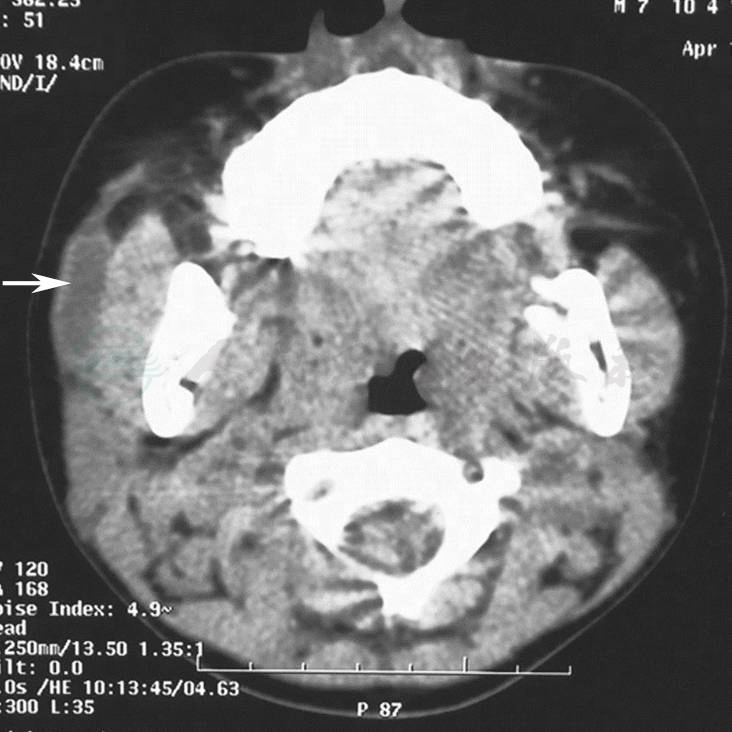

唾液腺造影显示腮腺或下颌下腺主导管囊状扩张,可以延及某些叶间导管。无继发感染史者,导管壁光滑(图1、2)。有继发感染史者,导管壁变得不光整。B超显示导管所在处无回声团块,呈管状结构(图3)。CT表现为沿导管走行方向呈管状的软组织病变(图4)。

图4先天性腮腺导管扩张(CT)

显示为沿腮腺导管走行方向呈管状的软组织病变